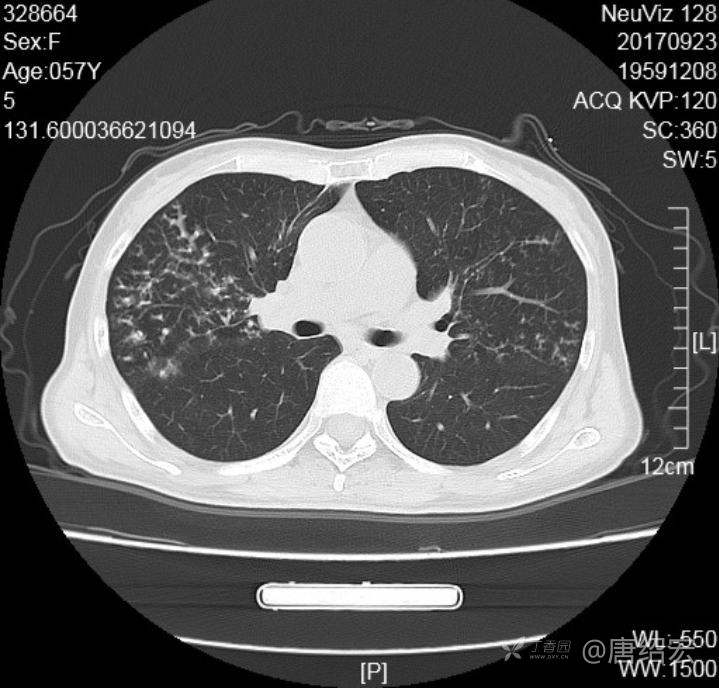

中年女性满肺树芽征还有支气管扩张,考虑什么疾病?

女,57岁,

主诉:发热、咳嗽、咯黄痰,胸闷3天入院。